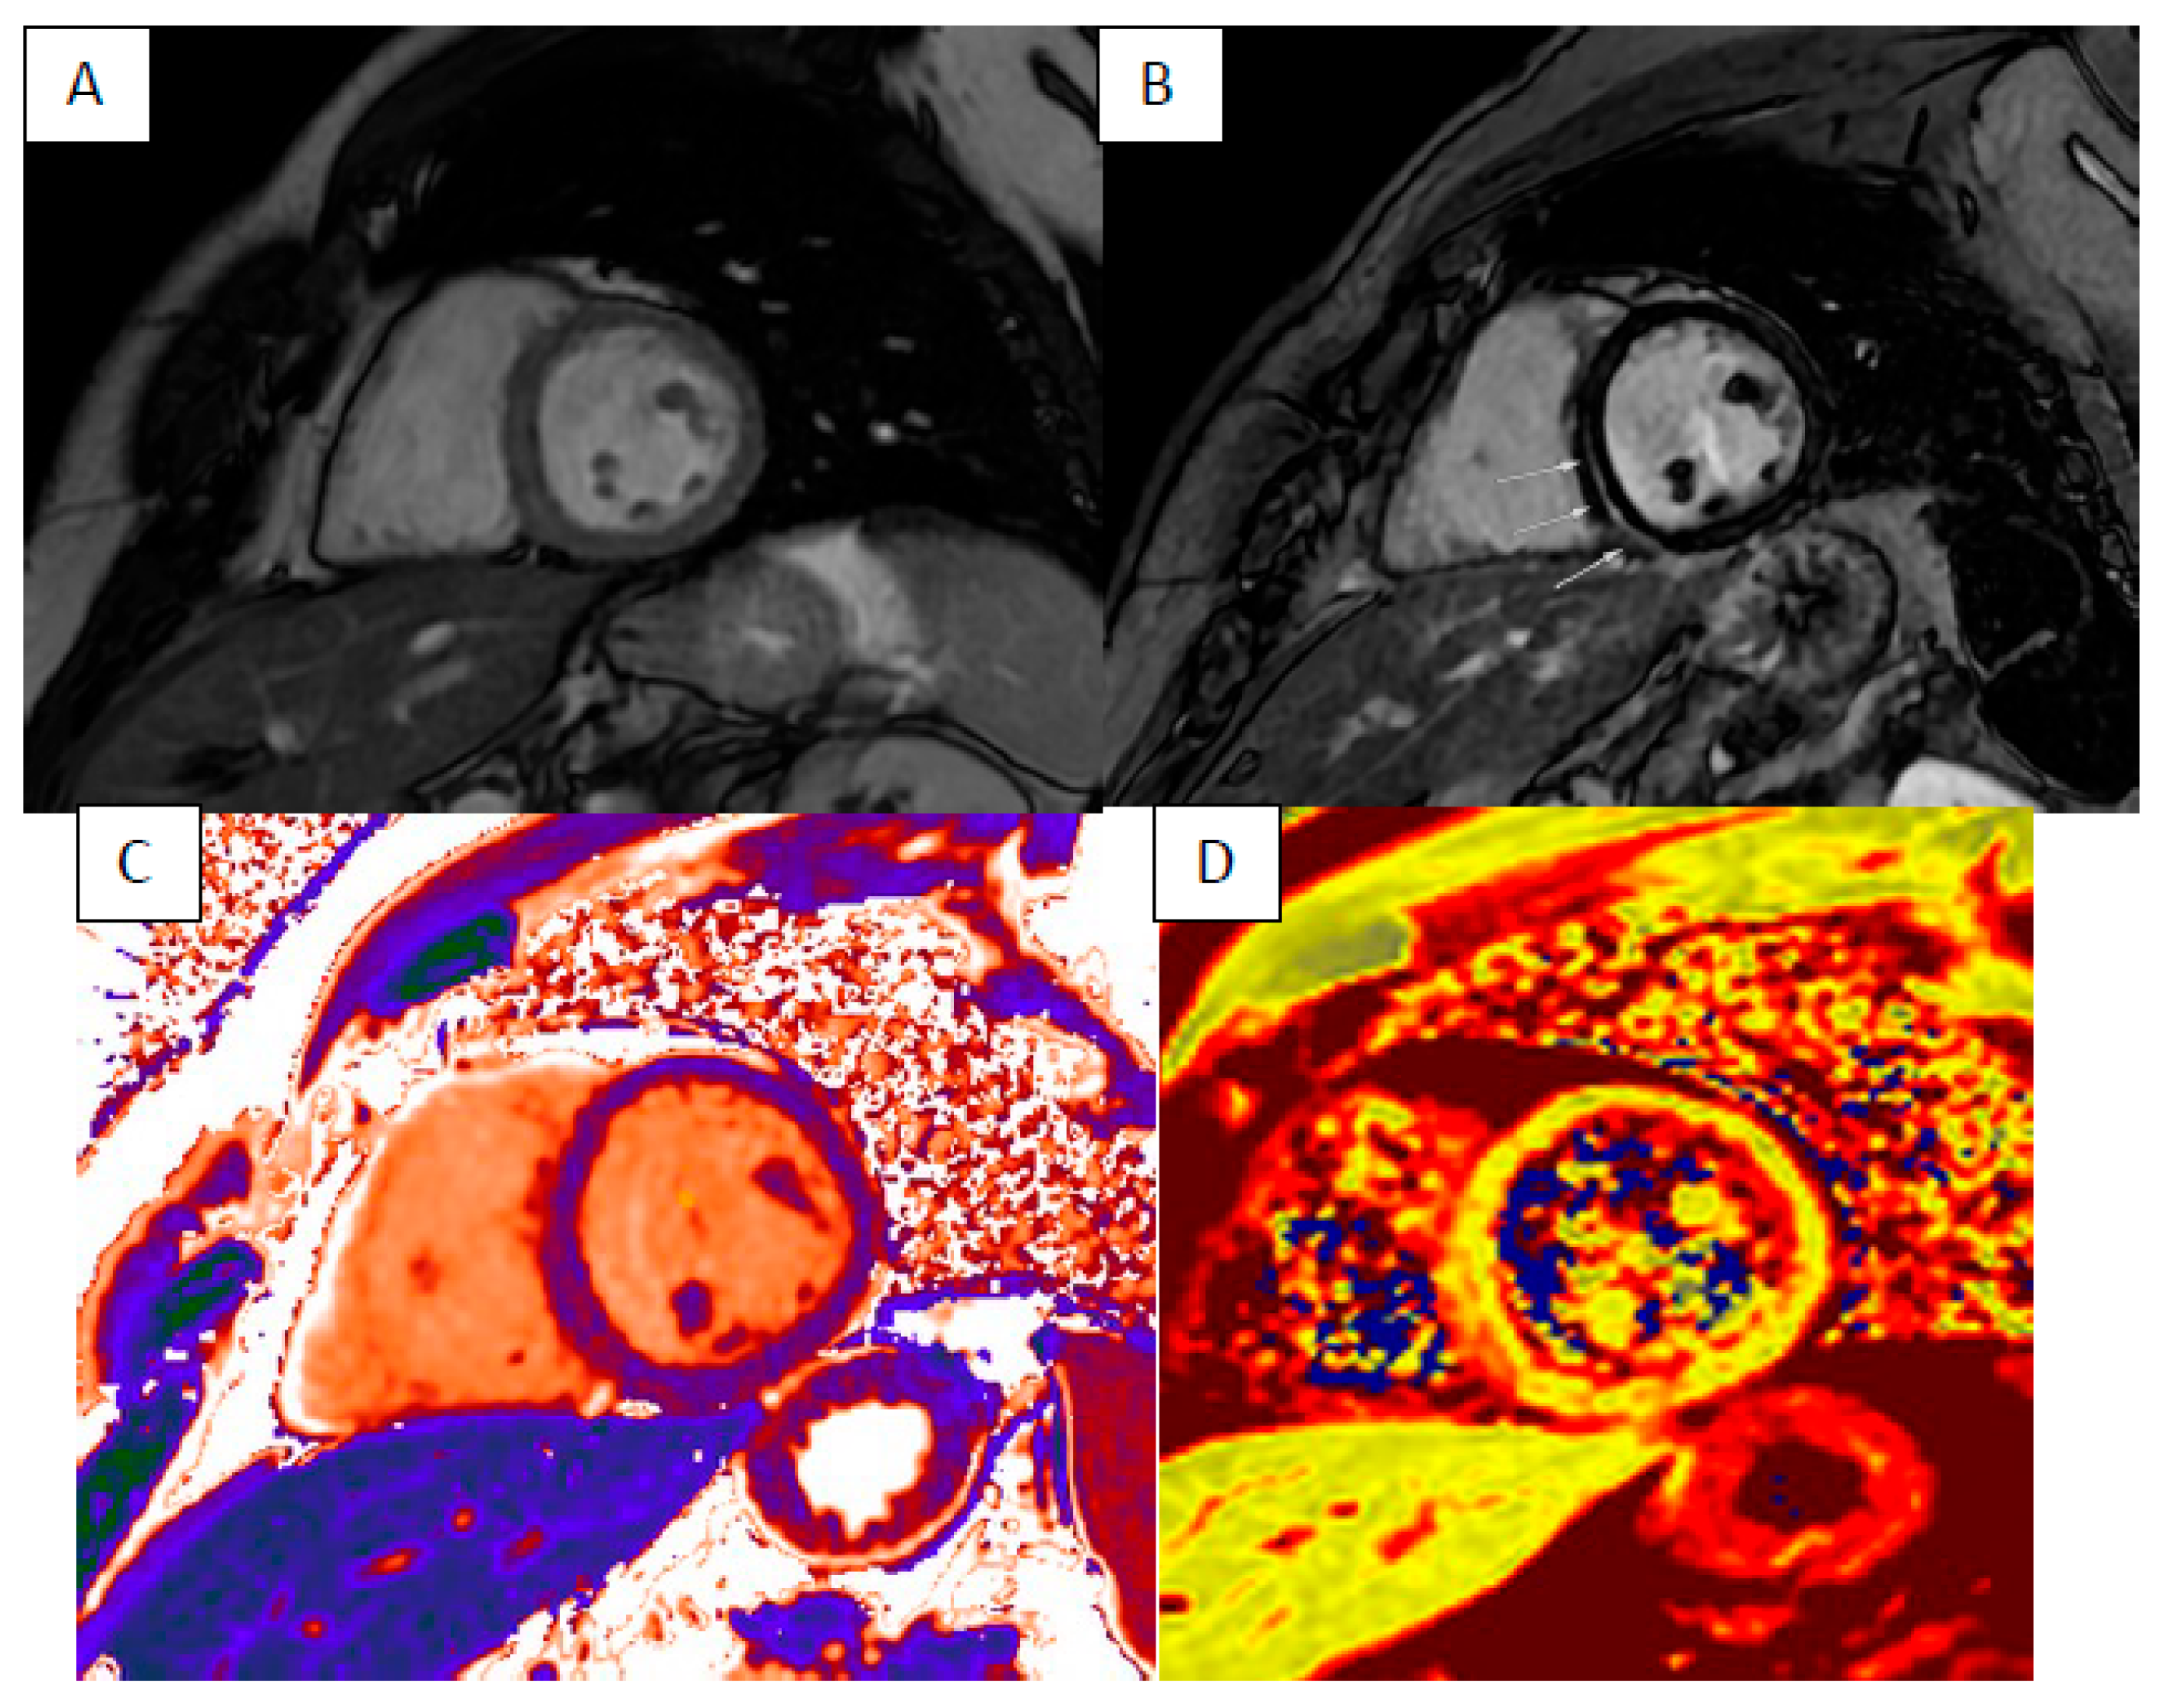

6. Myocardial Iron Overload